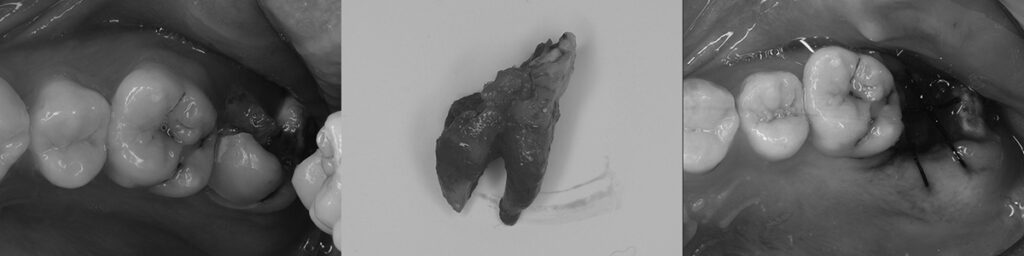

参考) 腐食した上顎第二大臼歯部に後方埋伏智歯を挺出矯正させ置き換えた例1

参考) 腐食した上顎第二大臼歯部に後方埋伏智歯を挺出矯正させ置き換えた例2